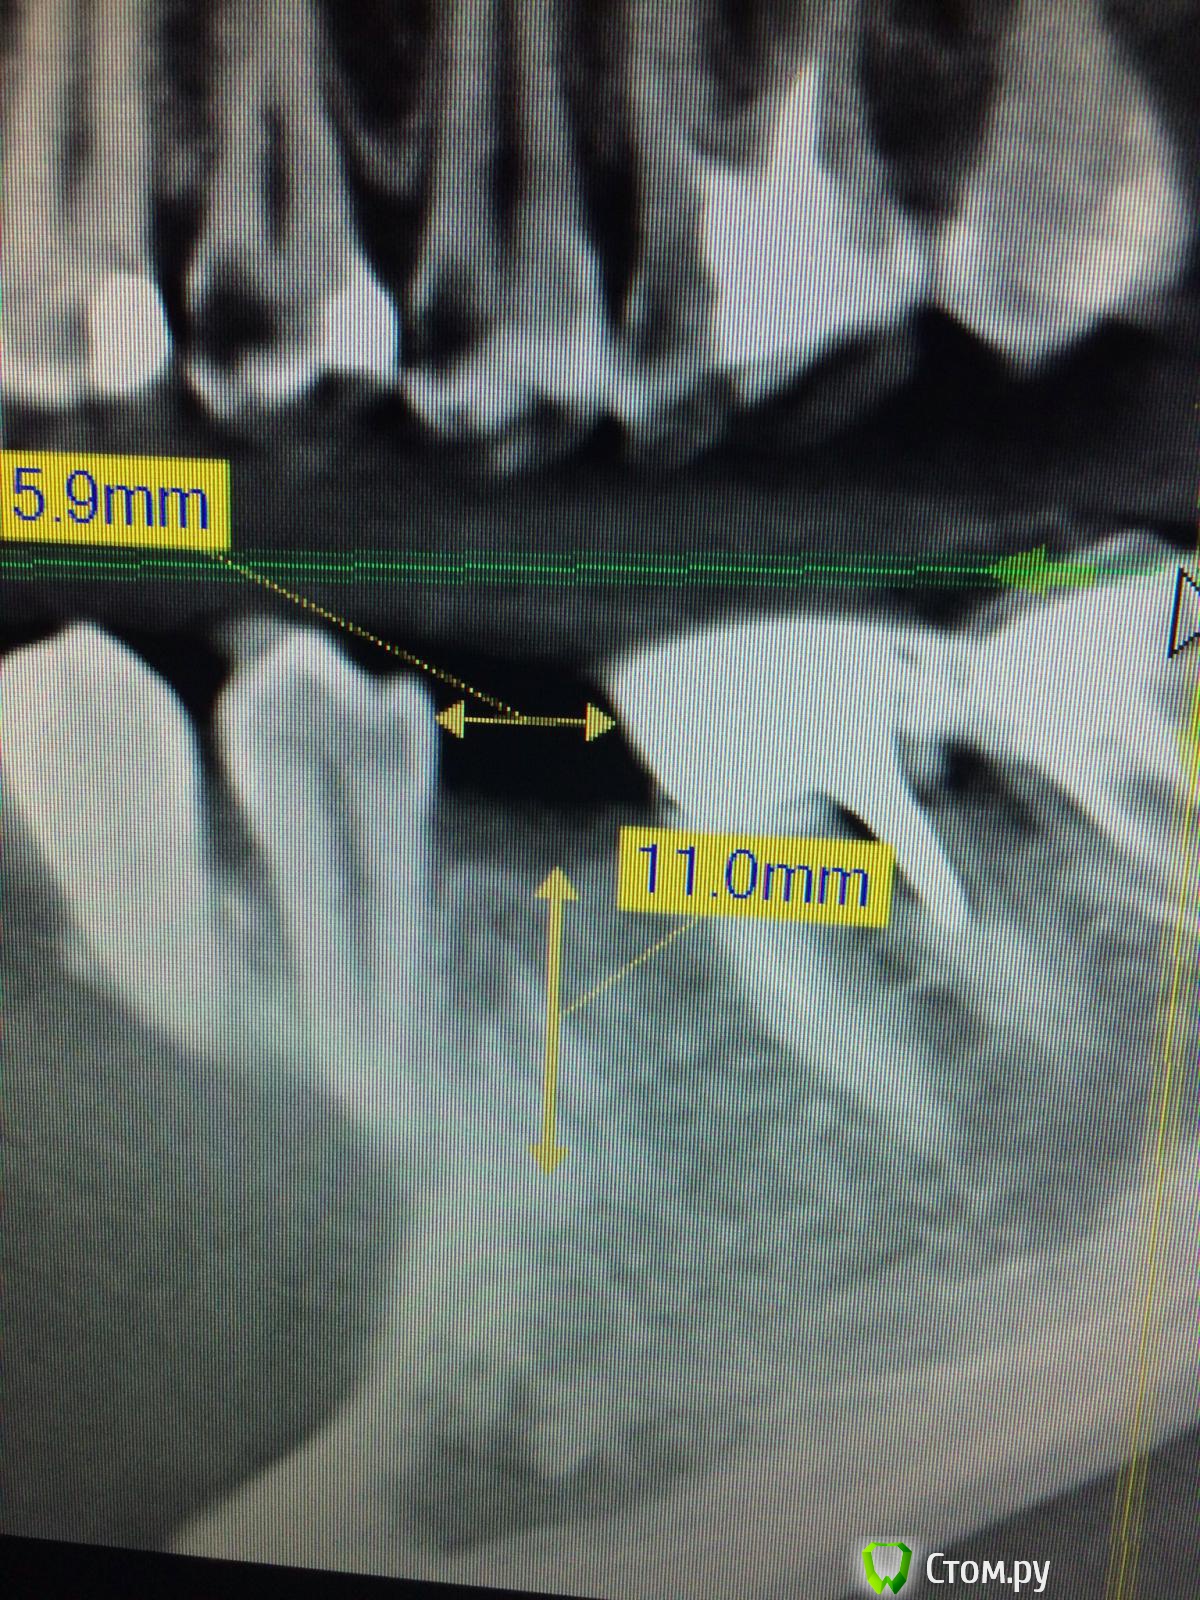

Vadim09 Опубликовано 3 октября, 2014 Поделиться Опубликовано 3 октября, 2014 (изменено) В области 3.5 отсутствует зуб, планирую поставить имплантиум 3.8, с расщеплением и подсадкой кости мис 4bone и мембраной от мис, подскажите тонкости, чтобы не сделал ошибку и простите, если вопрос не корректный. Изменено 3 октября, 2014 пользователем Vadim09 Ссылка на комментарий

doc-евгений Опубликовано 4 октября, 2014 Поделиться Опубликовано 4 октября, 2014 Имплантат 3.6 с нкр, без расщепления. Гребень с поднутрением, большая вероятность отлома. Ссылка на комментарий

k.t.m. Опубликовано 4 октября, 2014 Поделиться Опубликовано 4 октября, 2014 Спасибо, воспользовался вашим советом, кортикалка лопнула у шейки немног, пдсыпал биоосса и покрыл мембранойimage.jpgimage.jpgнадо было заглубить и более медиальнее 3 Ссылка на комментарий

Vadim09 Опубликовано 4 октября, 2014 Автор Поделиться Опубликовано 4 октября, 2014 (изменено) надо было заглубить и более медиальнееТоже так подумал, какя-то боязнь задеть корни, после того как у одного опытного доктора увидел.Когда раскрою, выложу фото и буду рад критике и советам Изменено 4 октября, 2014 пользователем Vadim09 Ссылка на комментарий